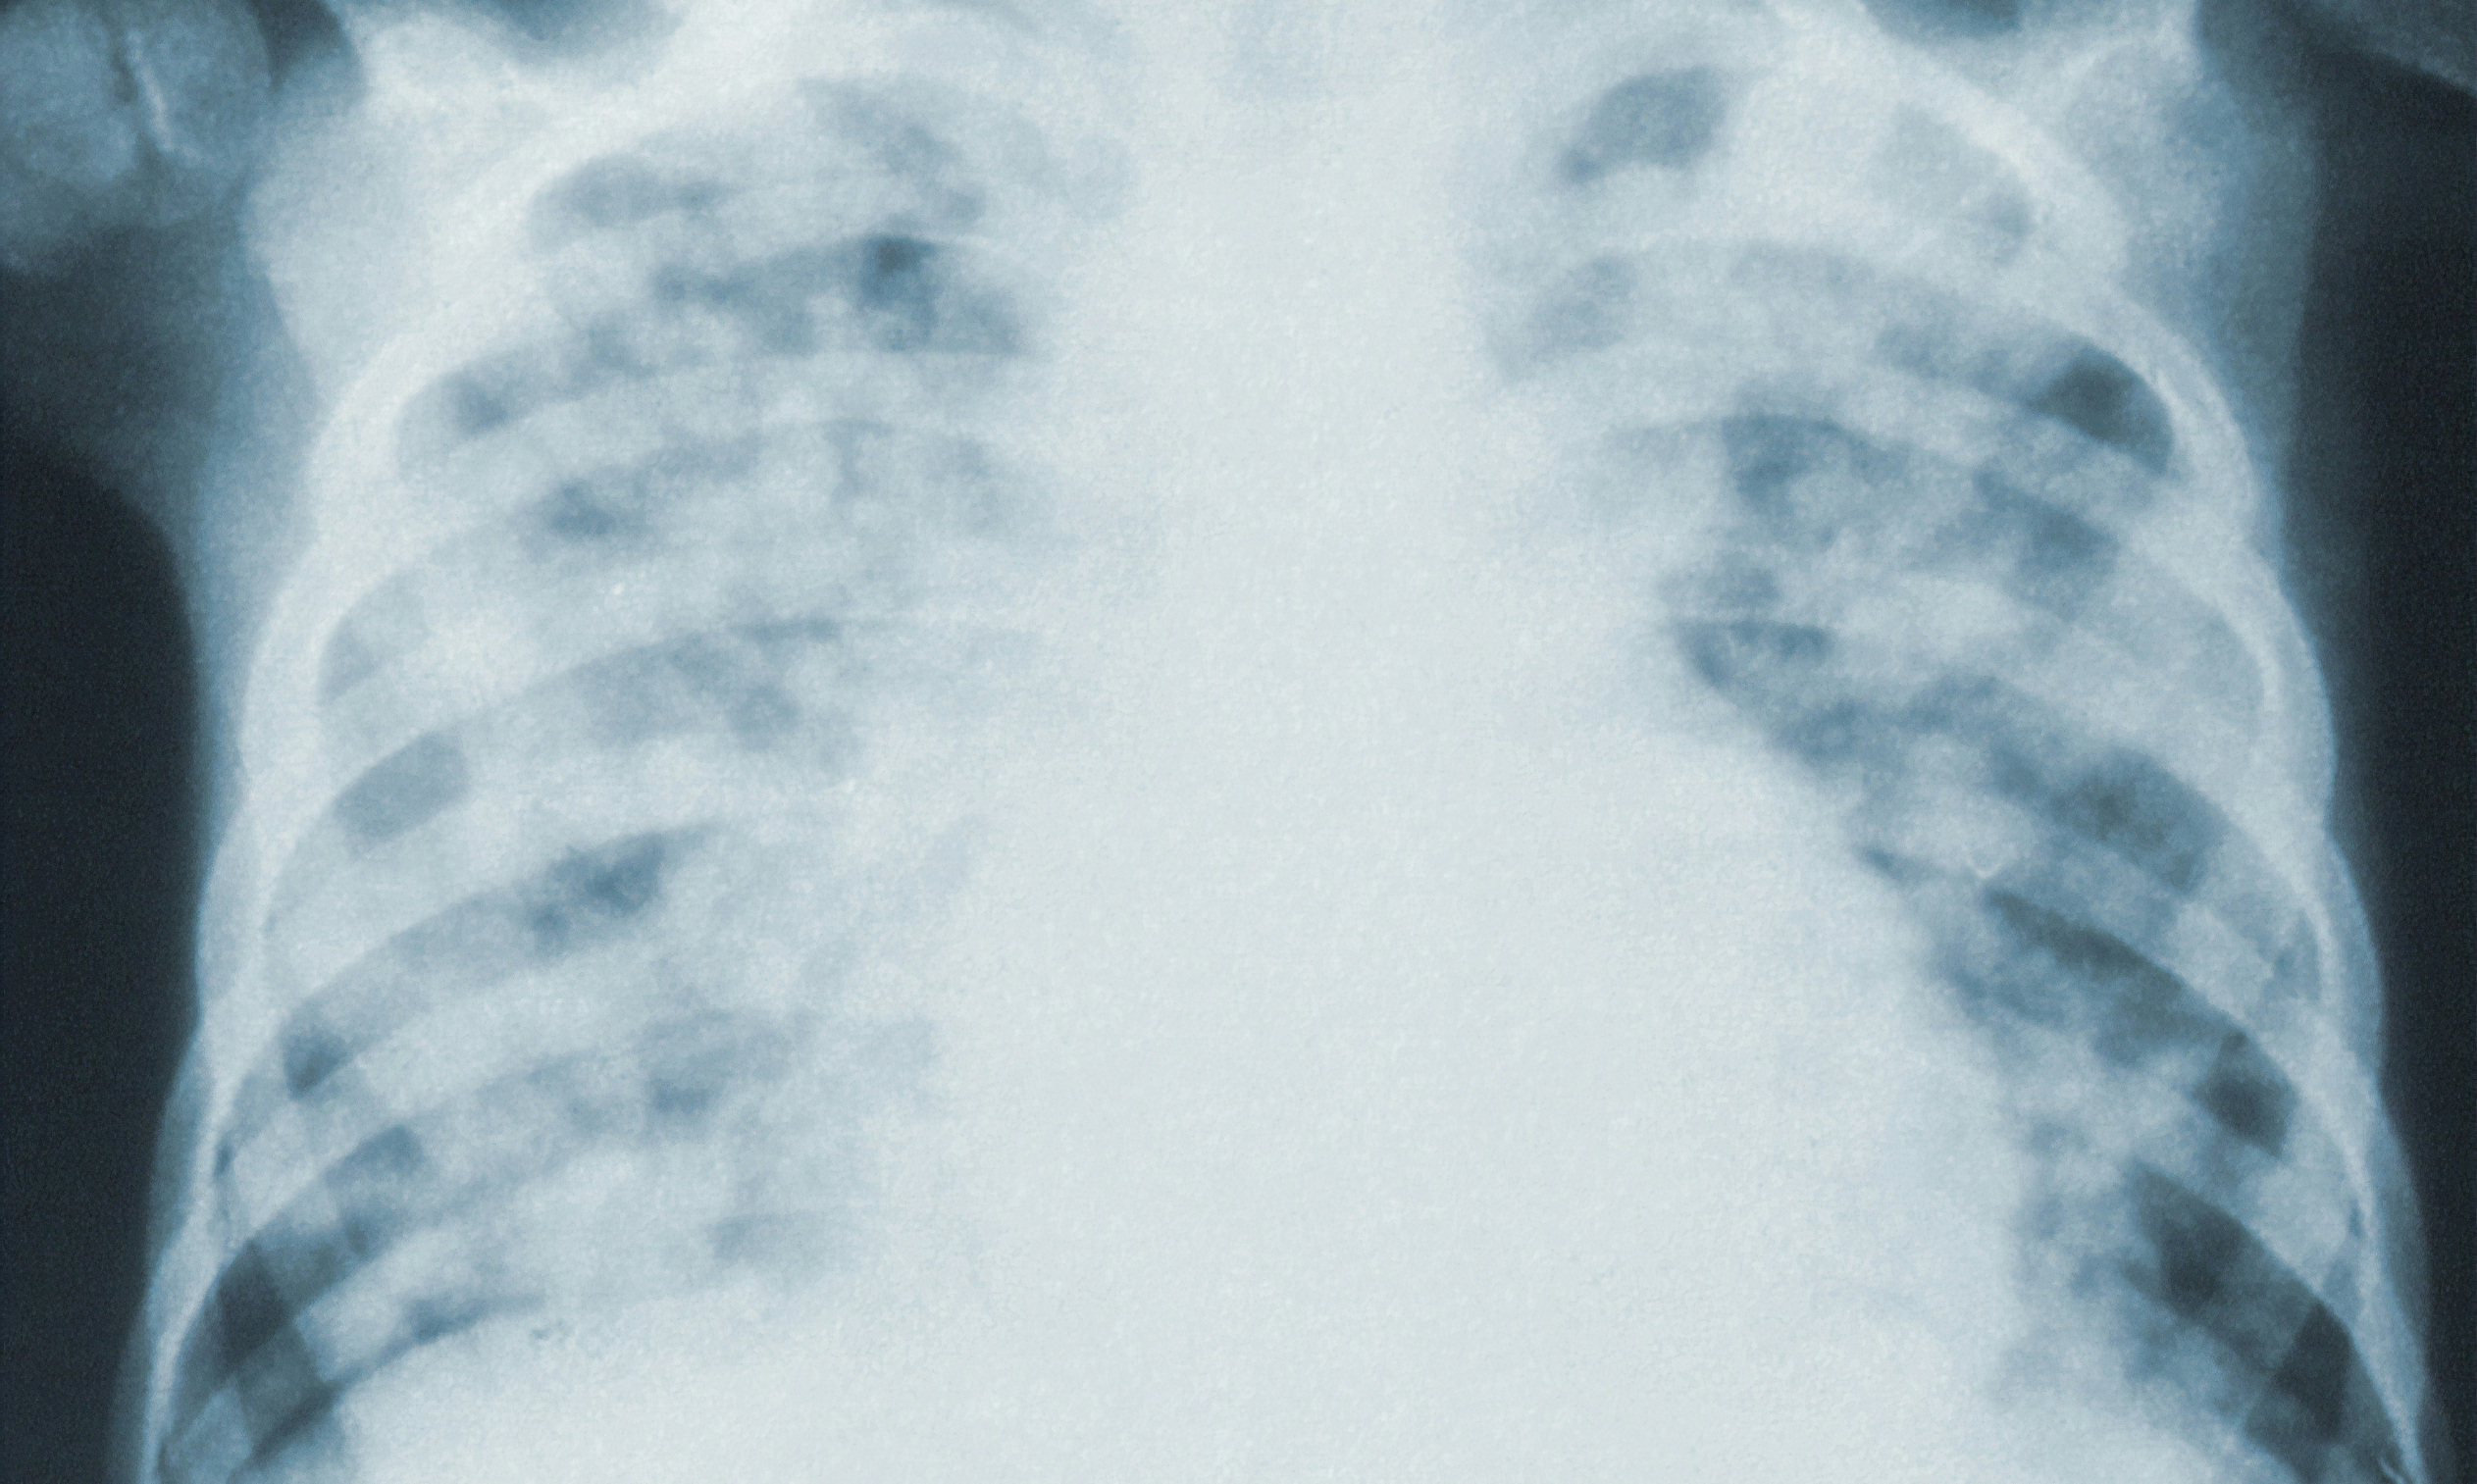

폐렴(pneumonia)은 폐의 기피조직에서 발생하는 염증으로, 세균, 바이러스, 곰팡이, 기타 미생물에 의해 촉발됩니다. 폐렴은 폐포들이 염증 반응으로 인해 산소를 올바르게 흡수하고 이산화탄소를 방출하는 데 어려움을 겪을 수 있는 심각한 질환입니다.

폐렴의 증상은 기침, 가래, 호흡 곤란, 가슴 통증, 발열, 흉통, 피로감 등이 있을 수 있습니다. 심한 경우에는 혈액 산소 농도가 낮아져 청색증이 발생할 수도 있습니다.